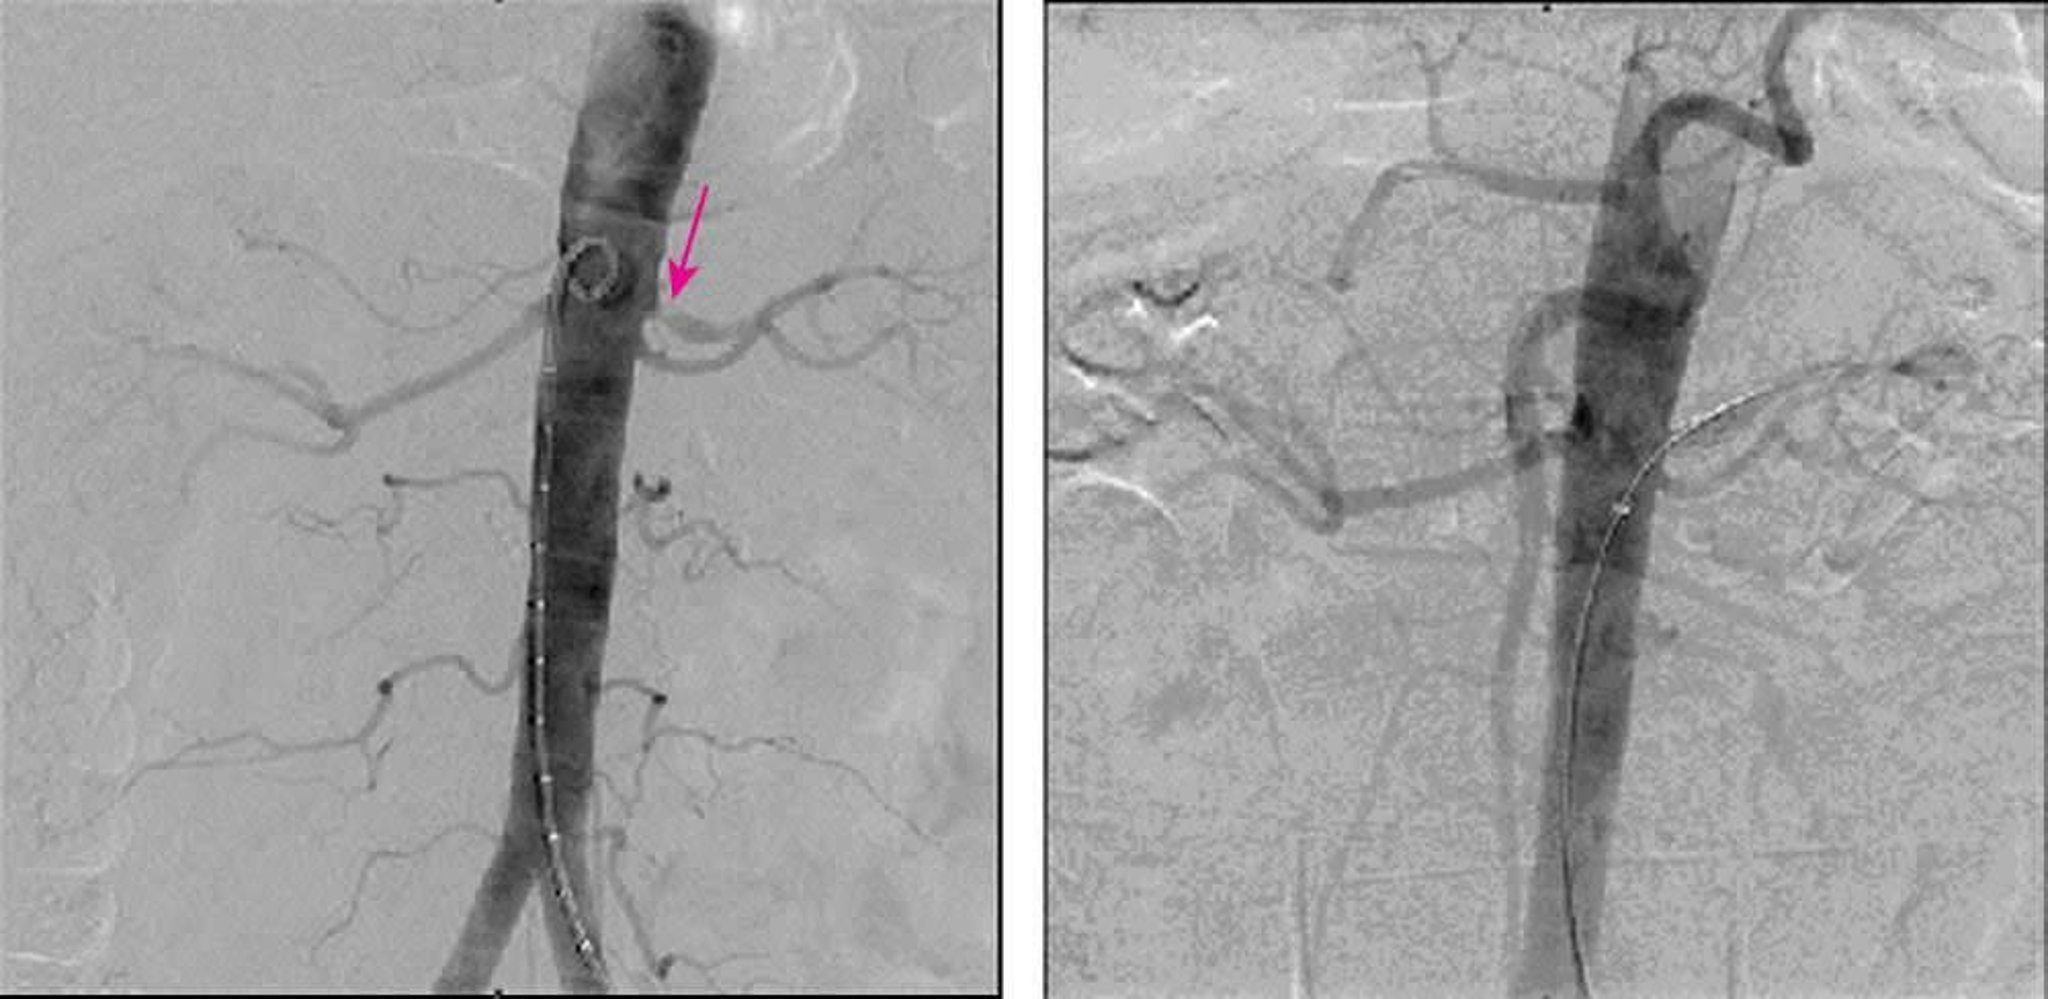

Стеноз почечной артерии (цифровая субтракционная ангиография)

На левом снимке, полученном методом цифровой субтракционной ангиографии, выявлен стеноз левой почечной артерии до 90%. На правом снимке показано полное устранение стеноза после установления стента.

Image provided by Jan N. Basile, MD.